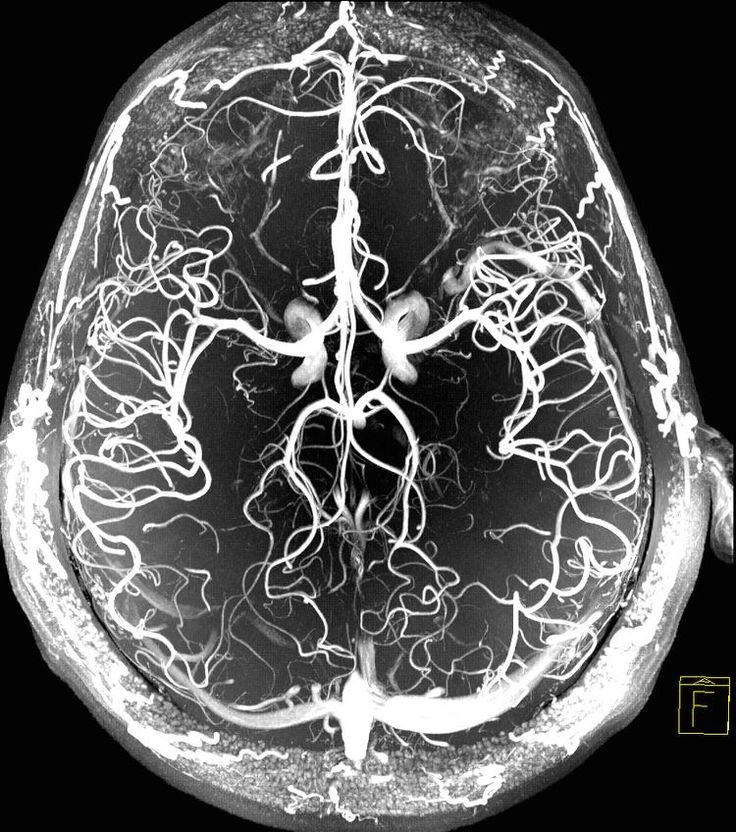

脳腫瘍、脳血管障害、脊椎脊髄疾患、頭部外傷、水頭症、頭痛、など脳神経外科一般に対応しています。 MRI、CT、シンチグラフィー、PETなどの最新の画像診断が可能です。

脳動脈瘤とは、脳の血管が一部ふくらみ、コブ状になったものです。未破裂の状態では症状が出ないことが多く、健康診断や脳ドックで偶然見つかるケースが増えています。ただし、破裂するとくも膜下出血という重篤な状態を引き起こすため、適切な評価と治療の判断が重要です。

頚動脈は、脳に血液を送る重要な血管です。この血管が動脈硬化によって狭くなる状態を「頚動脈狭窄症」といいます。多くは無症状ですが、脳への血流が低下し、一時的な麻痺(TIA)や脳梗塞の原因になることがあります。